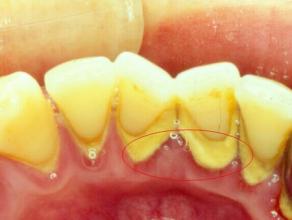

预防牙结石的方法有哪些?由于食物残渣长期在牙齿表面堆积,不及时清理,就容易形成牙结石,影响口腔健康。大连康贝佳口腔医生介绍:牙结石是可以预防的,那么预防牙结石有什么方法?下面就让大连康贝佳口腔医生为您详细介绍。

1、人们要想有效的预防牙结石的发生,这时就需要人们保障在早、晚刷牙。并且还要在饭后漱口,同时对于有需要的使人们来说,还可以采用牙线的方法进行洁牙。

2、如果预防牙结石失败,这时同样也是能使用洗牙的治疗办法来进行治疗。并且人们在进行洗牙的方法还能对口腔内的牙结石达到治疗粉碎的效果,同时,在治疗时不会对人们又的副作用情况发生。

大连康贝佳口腔在洁牙方面所使用的是高频声呐洁牙仪,该技术能进行治疗解决牙结石的发生,同时洁牙还可以修复口腔内的牙周病情况,让患者的牙齿更健康。